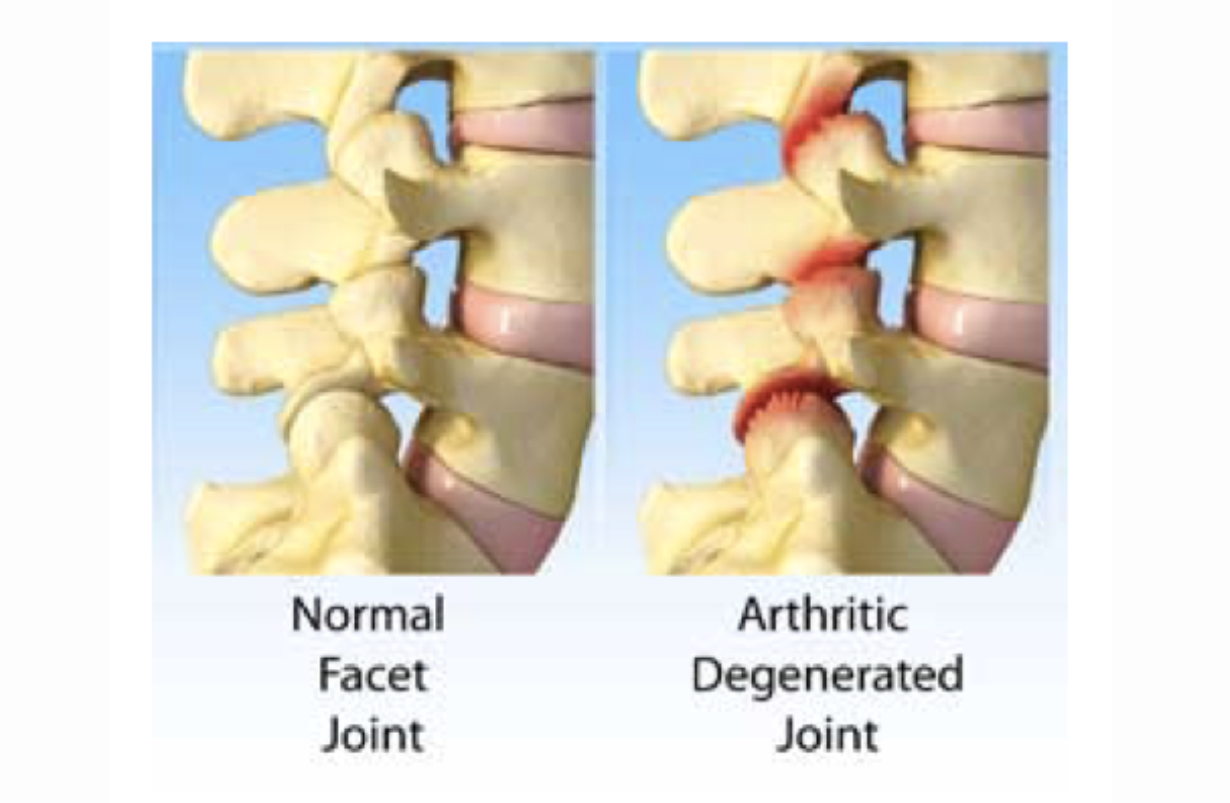

Facet Syndrome

Painful difficulty in moving one or more facet joints, the small joints at the back of the vertebrae. This occurs either from arthritis or muscle spasm. These are the small joints at the top and bottom, and to the right and left of each vertebra, that interface with the same joints in the vertebrae above and below. When they swell in arthritis, they narrow the central spinal canal, and are an element in central spinal stenosis.